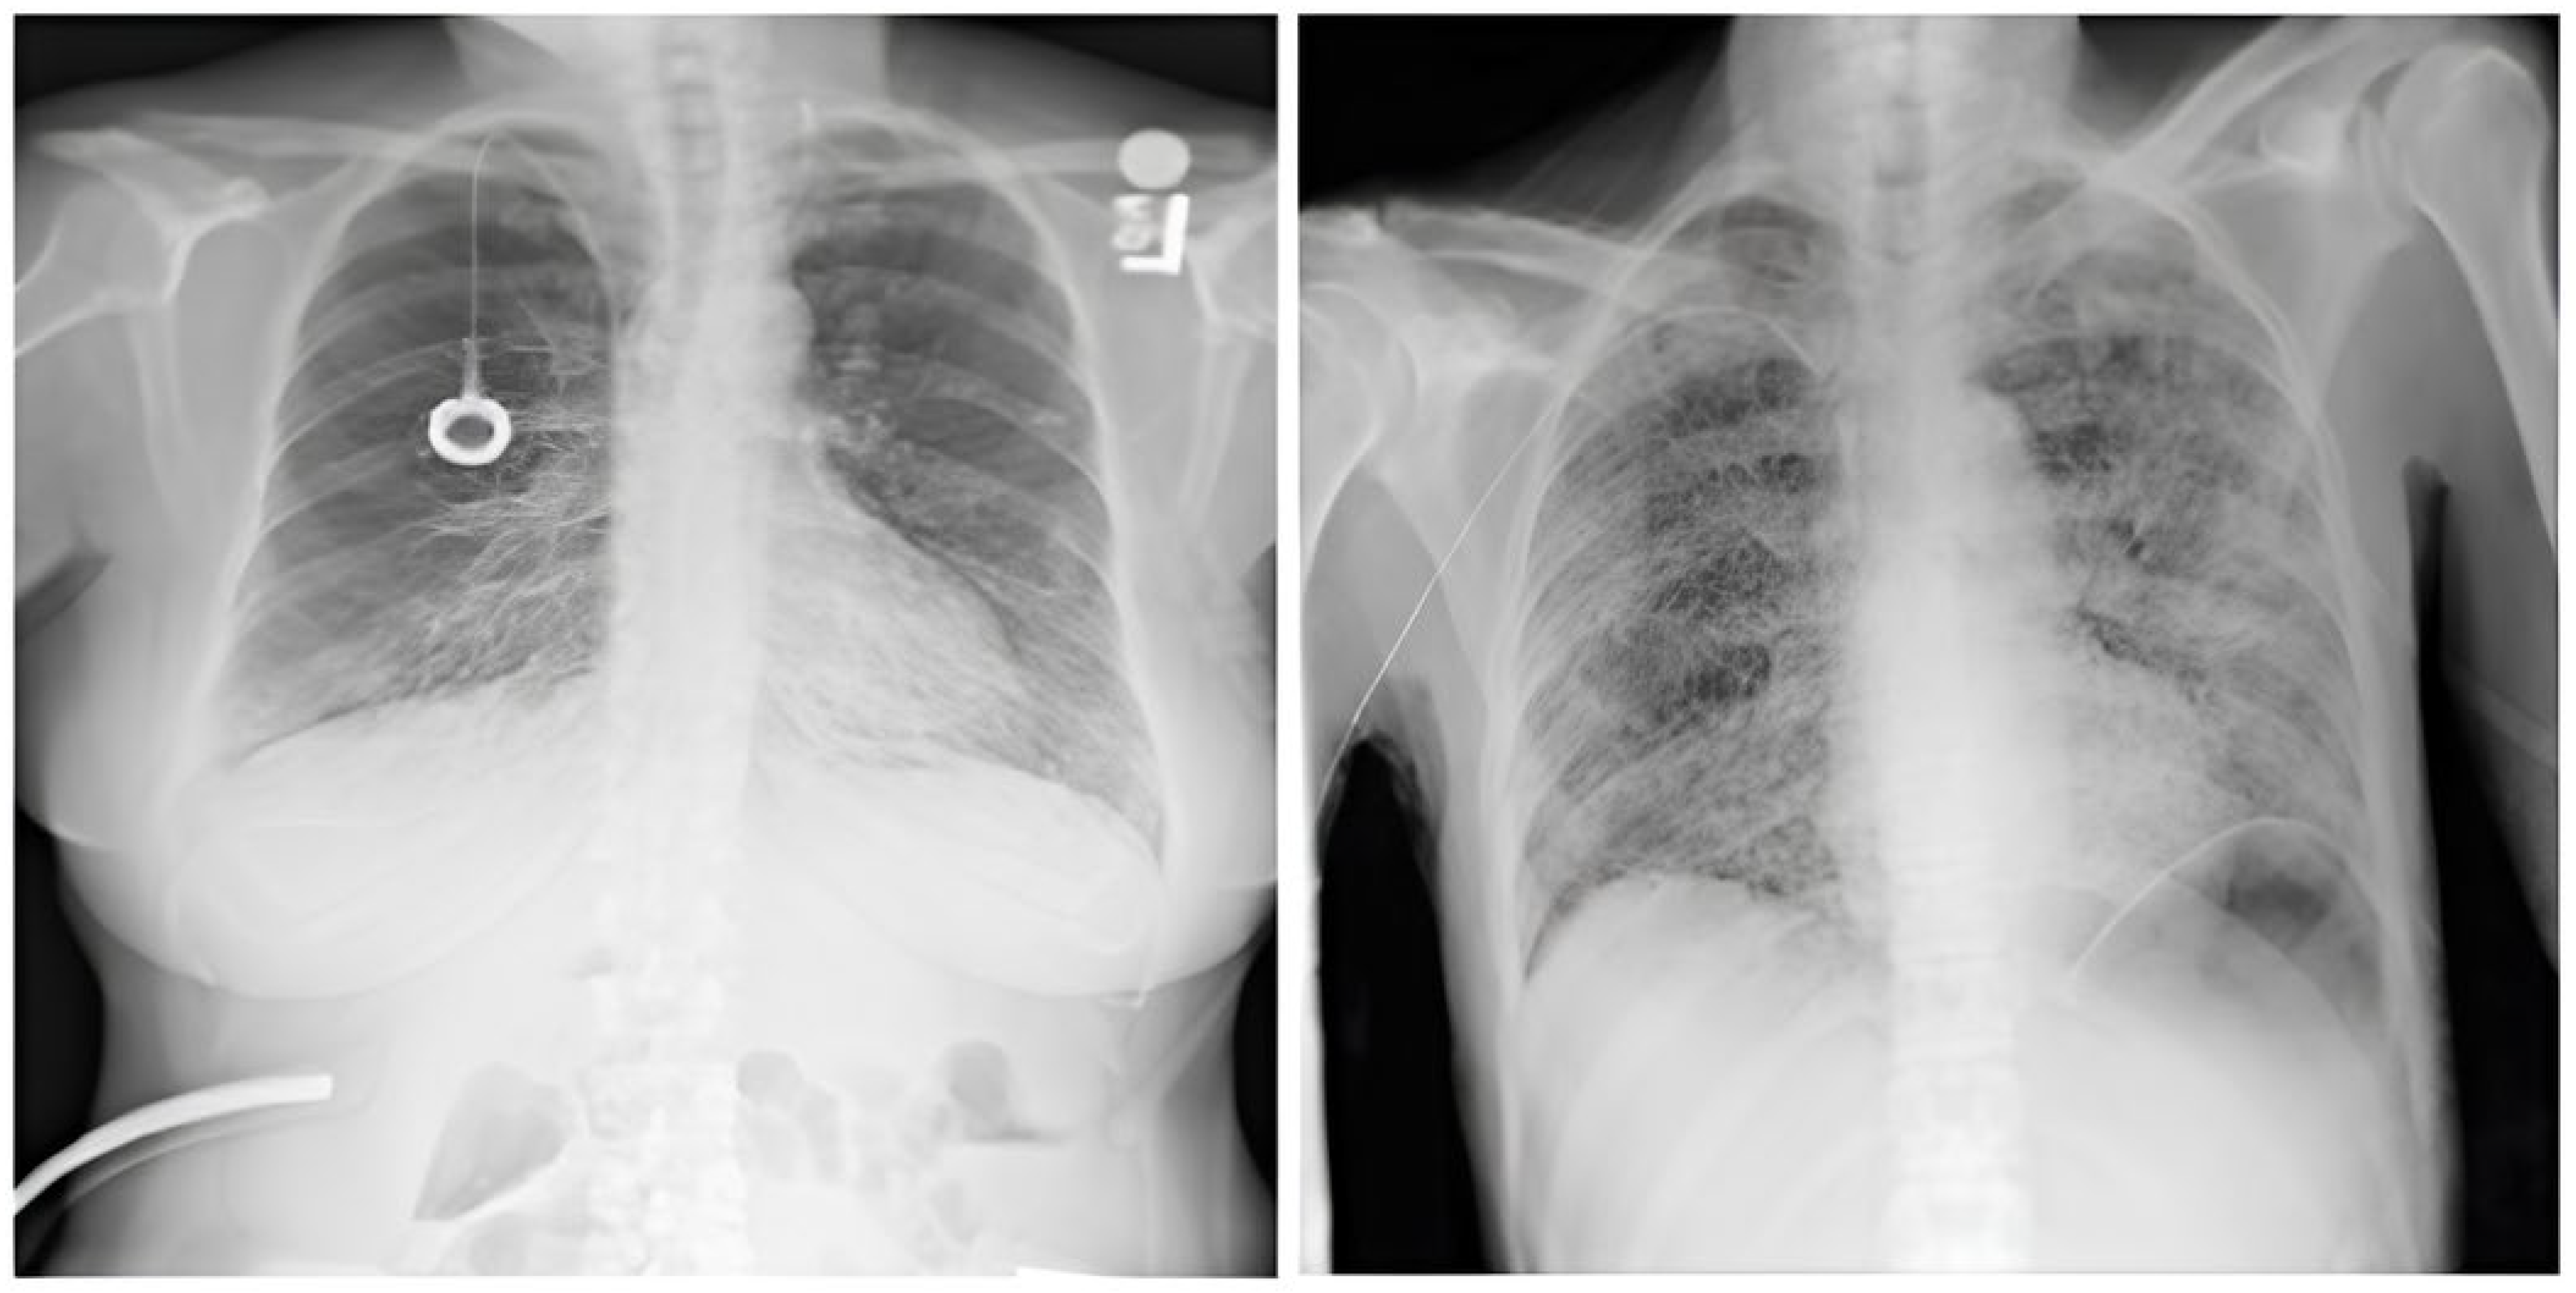

3.1.1. CXR NIH Dataset

The dataset comprises 112,120 X-ray images with disease labels from 30,805 unique patients [21]. The samples from the CXR NIH dataset are shown in Figure 3. Disease labels were extracted from radiology reports using NLP, achieving over 90% accuracy and supporting weakly supervised learning.

Figure 3.

CXR NIH dataset samples [21].

3.1.2. CheXpert Dataset

This is an extensive and meticulously curated collection comprising 224,316 chest radiographs obtained from 65,240 patients who underwent radiographic examinations at Stanford Health Care facilities over a substantial timeframe spanning from October 2002 to July 2017 [24,25]. The samples from the CheXpert dataset are shown in Figure 4. These examinations were performed across a diverse range of settings, including inpatient and outpatient centers, ensuring the inclusion of a broad spectrum of clinical scenarios and patient demographics. Each radiograph in this dataset has been labeled for 14 distinct, standard chest radiographic observations, aligning with established clinical guidelines and fostering consistency in labeling across the dataset.

Figure 4.

CheXpert dataset samples [24].

3.1.3. CXR VinDr Dataset

This was developed to provide the research community with a large-scale, high-quality collection of CXR images annotated with detailed and reliable labels [26]. The samples from the CXR VinDr dataset are shown in Figure 5. This dataset was constructed using over 100,000 raw images in DICOM format, which were retrospectively collected from two of Vietnam’s largest and most prominent hospitals: Hospital 108 and Hanoi Medical University Hospital [27]. These facilities contributed to the dataset’s diversity and representativeness by including many cases and patient demographics.

Figure 5.

VinDr-CXR Dataset samples [26].